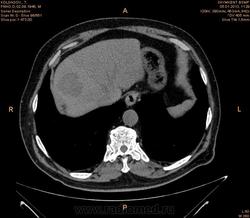

Помогите разобраться.Больной 2 мес назад обследован на узи бр.полости  чисто.(м.б. не опытный узист.)Беспокоять боль в правом подреберье, потеря веса нет.Анализы еще не готовы.

Гиподенсное образование в 8 сегменте, с накоплением по контуру в артериальную фазу, заполнением почти полностью в портальную, и опять гипо- в отсроченную. Пока думается на гемангиому, дифференцировать с гепатоцелюллярным раком, несмотря на отсутствие признаков цирроза. Сложновато  без дайкома.

Судя по времени, отсроченная через 7-8 мин от начала введения контраста (ФИО пациента убирайте, пожалуйста!). На мета, на мой взгляд, не похоже. Подождём, что еще коллеги скажут.

Вымывание контраста к венозной и равновесной фазам если не путаю более характрено для HCC.

имеет значение количество и скорость введения контраста

без диком создается впечатление что контраста либо мало было либо низкая скорость